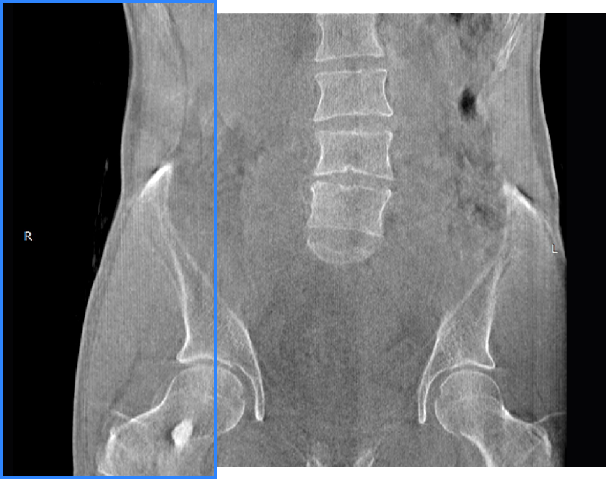

髋关节

FOV 250mm

FOV 350mm